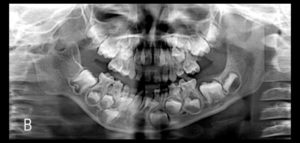

91- Anquilosis de la articulación temporomandibular como una complicación de la artritis séptica neonatal

La artritis séptica es una infección purulenta de alguna articulación, la cual se produce cuando los microorganismos invaden el espacio de alguna articulación, ya sea